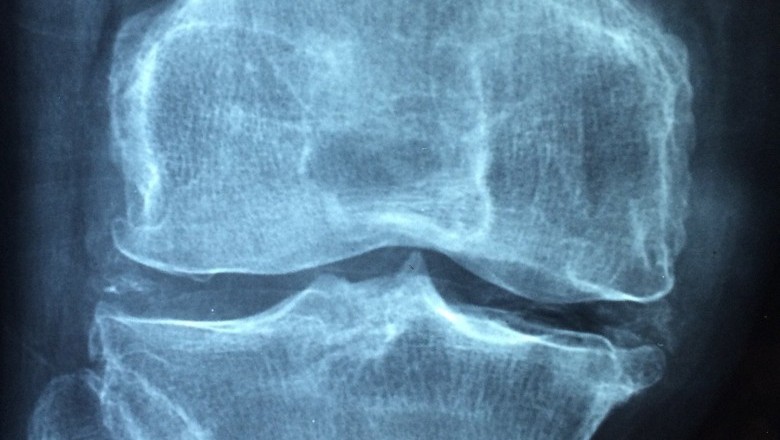

Du Huo Ji Sheng Wan is also applicable for the stiffness of legs and waist. It is suggested for the patients who are suffering from spasmodic pain in bones and muscles, weakness of lower extremities and knees and for pain in the knees and back. All the ingredients that are used in the manufacturing of Du Huo Ji Sheng Wan are the herbs and roots of very good quality with excellent medicinal value. The major ingredients that are used in the production of Du Huo Ji Sheng Wan include Pubescent Angelica, Codonopsis, Lorunthus, Cortex Eucommia E, and Poria.

Pubescent Angelica is known to be the prime ingredient of Du Huo Ji Sheng Wan. It is actually a dried root extracted from Angelica Pubescen Maxim. This root is considered to be best for rheumatic arthritis comprising of pain in knees and lower back. There is quiet a number of people who suffer from head ache and precordial pain due to the attack of extreme cold. Pubescent Angelica is a good medicine for the various problems related with it.